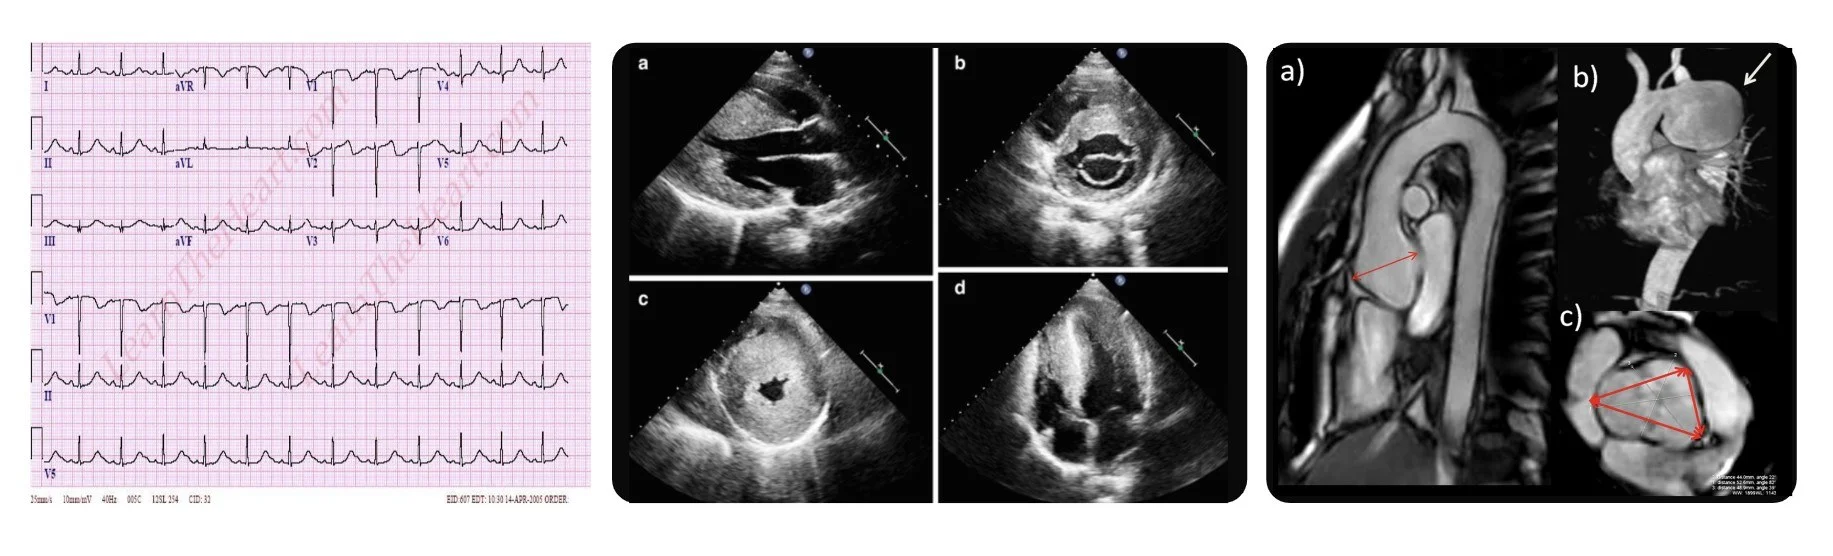

A 50-year-old East Asian female patient was reffered for exome sequencing. She had left ventricular hypertrophy, hypertrophic cardiomyopathy and short PR with T inversion on EKG as you can see in these figures. She had only received conservative treatments to relieve her symptoms. There was no previous genetic testing performed and exome sequencing was ordered as proband-only withour any other family members for testing.

You should all know what these figures are showing. EKGs and imaging such as echocardiogram, CT and MRI definitely provide important information about patient’s current cardiac condition and help with the diagnosis and managements.